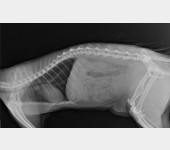

Trzy lata temu odłowiłam na osiedlu do sterylizacji dziką około 2letnią kotkę, która nazwaliśmy LUSI. Okazało się, że ma gorączkę, zapalenie płuc i inne przypadłości kota dziko - żyjącego. Z uwagi na konieczność leczenia, LUSIA zamieszkała z nami. Bardzo szybko zaadoptowała się do nowych warunków, więc została z nami. W tym roku zrealizowałam moje marzenie i przeprowadziłam się do mieszkania z ogródkiem. W trakcie prac wykończeniowych, przez nieuwagę pracownika wystraszona uciekła. Blisko 3 miesiące poszukiwałam ją bezskutecznie, aż do 18 marca Tego dnia szłam do domu i kotka słysząc mój głos, wyczołgała się z krzaków pod moje nogi ciągnąc za sobą tylną łapkę. Od razu udałam się do weterynarza i cios w serce... Okazało się, że LUSI została brutalnie, z wielką siłą potrącona przez samochód kilka tygodni wcześniej i pozostawiona w olbrzymim bólu i cierpieniu. Kotka po tym zdarzeniu zdziczała, ale nie dając za wygraną udałam się do znanego i polecanego specjalisty chirurga – ortopedy. Weterynarz zaleciła dalszą diagnostykę neurologiczną, leczenie farmakologiczne i dała nadzieję na wyzdrowienie kotki po zoperowaniu jej pękniętej miednicy i łapki. Niestety z uwagi na trudną sytuację finansową, nie jestem w stanie sama podołać tym kosztom. Bardzo proszę o wsparcie, abym mogła ulżyć kotce w cierpieniu.